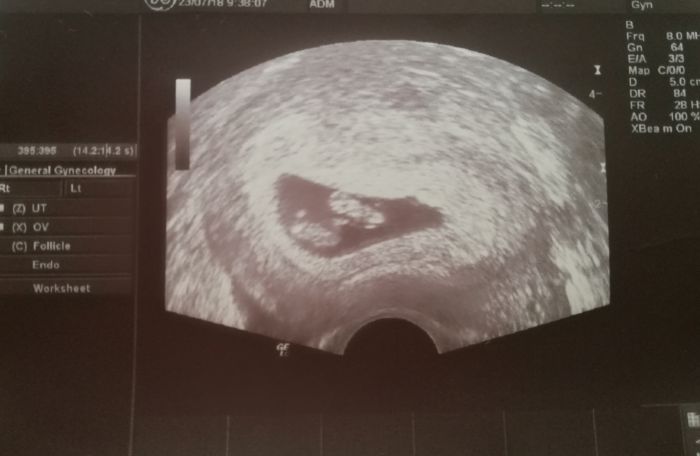

Ahoj holky, tak já se teď vrátila od doktora a jsem z toho nějaká zmatená. Podle PM bych měla být 6+2, ale podle doktora jsem 5+0. Ale zároveň řekl, že to nemusí nic znamenat, že se to nedá přesně takhle brzy změřit. Tak já nevím, jestli se mám radovat nebo ne. Podle mě by už to mělo být dobře zmeritelne, ne? Co si o tom myslíte? Kontrola az za 4 týdny. Přemýšlím, že pojedu do nemocnice, kde mi snad reknou víc a kde budou mit třeba lepší ultrazvuk.

Nene nebylo videt skoro nic, prý to nejde ještě ani změřit. A srdíčko už vubec ne

Mirco když jsem byla poprvé u mudra tak jsem měla bych 6+ něco a dle ultrazvuku jsem byla 5+4 a taky tam nic vidět nebylo o 14 dnů déle bylo vidět srdíčko a všechno bylo v pohodě

Holky,tak jsem byla v poradně aby mi potvrdil těhotenství a že je vše v pořádku a ŠOK . Já čekám dvojčata !!!! ? Takže můj pobyt na gyndě se prodloužil,začalo papírování a musím na genetiku v 11tt jestli jsou jedno nebo dvojvaječné. Jinak miminka jsou v pořádku odpovídají 8tt a srdíčka byla krásně vidět. Hrozně se bojím holky hrozně moc. Aby to zvládli a jak to pak všechno zvládnu já